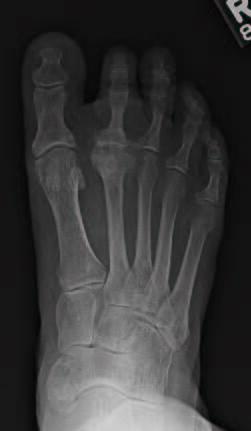

Degenerative joint disease (DJD) can be debilitating and result in functional deficits and low quality of life for the patient. DJD in the metatarsophalangeal joints (MPJ) of the foot has various treatment options, depending on the joint affected. Unfortunately, there are limited treatment options when specifically looking at DJD involving the less common second MPJ (see first photo above). Procedures to address arthritic pain at the second MPJ typically fall into two categories, either joint sparing or joint destructive. Treatment options vary depending on the preoperative pathology as well as patient-specific characteristics.